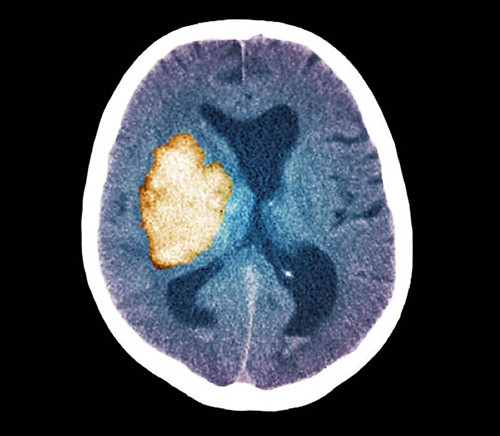

Hjerneslag representerer en økende byrde for helsevesenet i lavinntekts- og mellominntektsland. For å kunne forebygge sykdommen er det behov for kunnskap om risikofaktorer. Det finnes imidlertid lite data om risikofaktorer hos befolkningen i Afrika sør for Sahara. I en ny pasient-kontroll-studie har forskere kartlagt risikofaktorer for hjerneslag i Tanzanias største by, Dar-es-Salaam, og i det rurale Hai-distriktet nord i landet (1).

Totalt ble 200 pasienter med gjennomgått hjerneslag og 398 kontrollpersoner inkludert. Ujusterte analyser viste nokså like resultater for Dar-es-Salaam og Hai-distriktet. I den justerte analysen ble materialet analysert samlet. Tidligere hjerneslag eller TIA (OR 7,39; 95 % KI 2,42 – 22,53), hivinfeksjon (OR 5,61; 95 % KI 2,41 – 13,09), dyslipidemi, røyking og hypertensjon var signifikant assosiert med økt risiko for hjerneslag i den justerte analysen.

Ingen av de hivpositive hadde kjent infeksjon fra tidligere, og de var heller ikke under behandling med antiretrovirale medikamenter. Prevalensen av hypertensjon var høy, både hos dem som hadde gjennomgått hjerneslag (87 % i Dar-es-Salaam og 81 % i Hai) og hos kontrollpersonene (67 % og 70 %).

I en ledsagende kommentar understrekes det at assosiasjonen mellom hiv og hjerneslag er et viktig funn (2). Samtidig pekes det på at studien har svakheter – som at under halvparten av pasientene ble CT-undersøkt og at det manglet opplysninger om hivstatus for en stor del av dem. Det er derfor behov for videre studier for å bekrefte assosiasjonen, samtidig som arbeidet med reduksjon av hypertensjon og andre modifiserbare risikofaktorer bør styrkes (2).